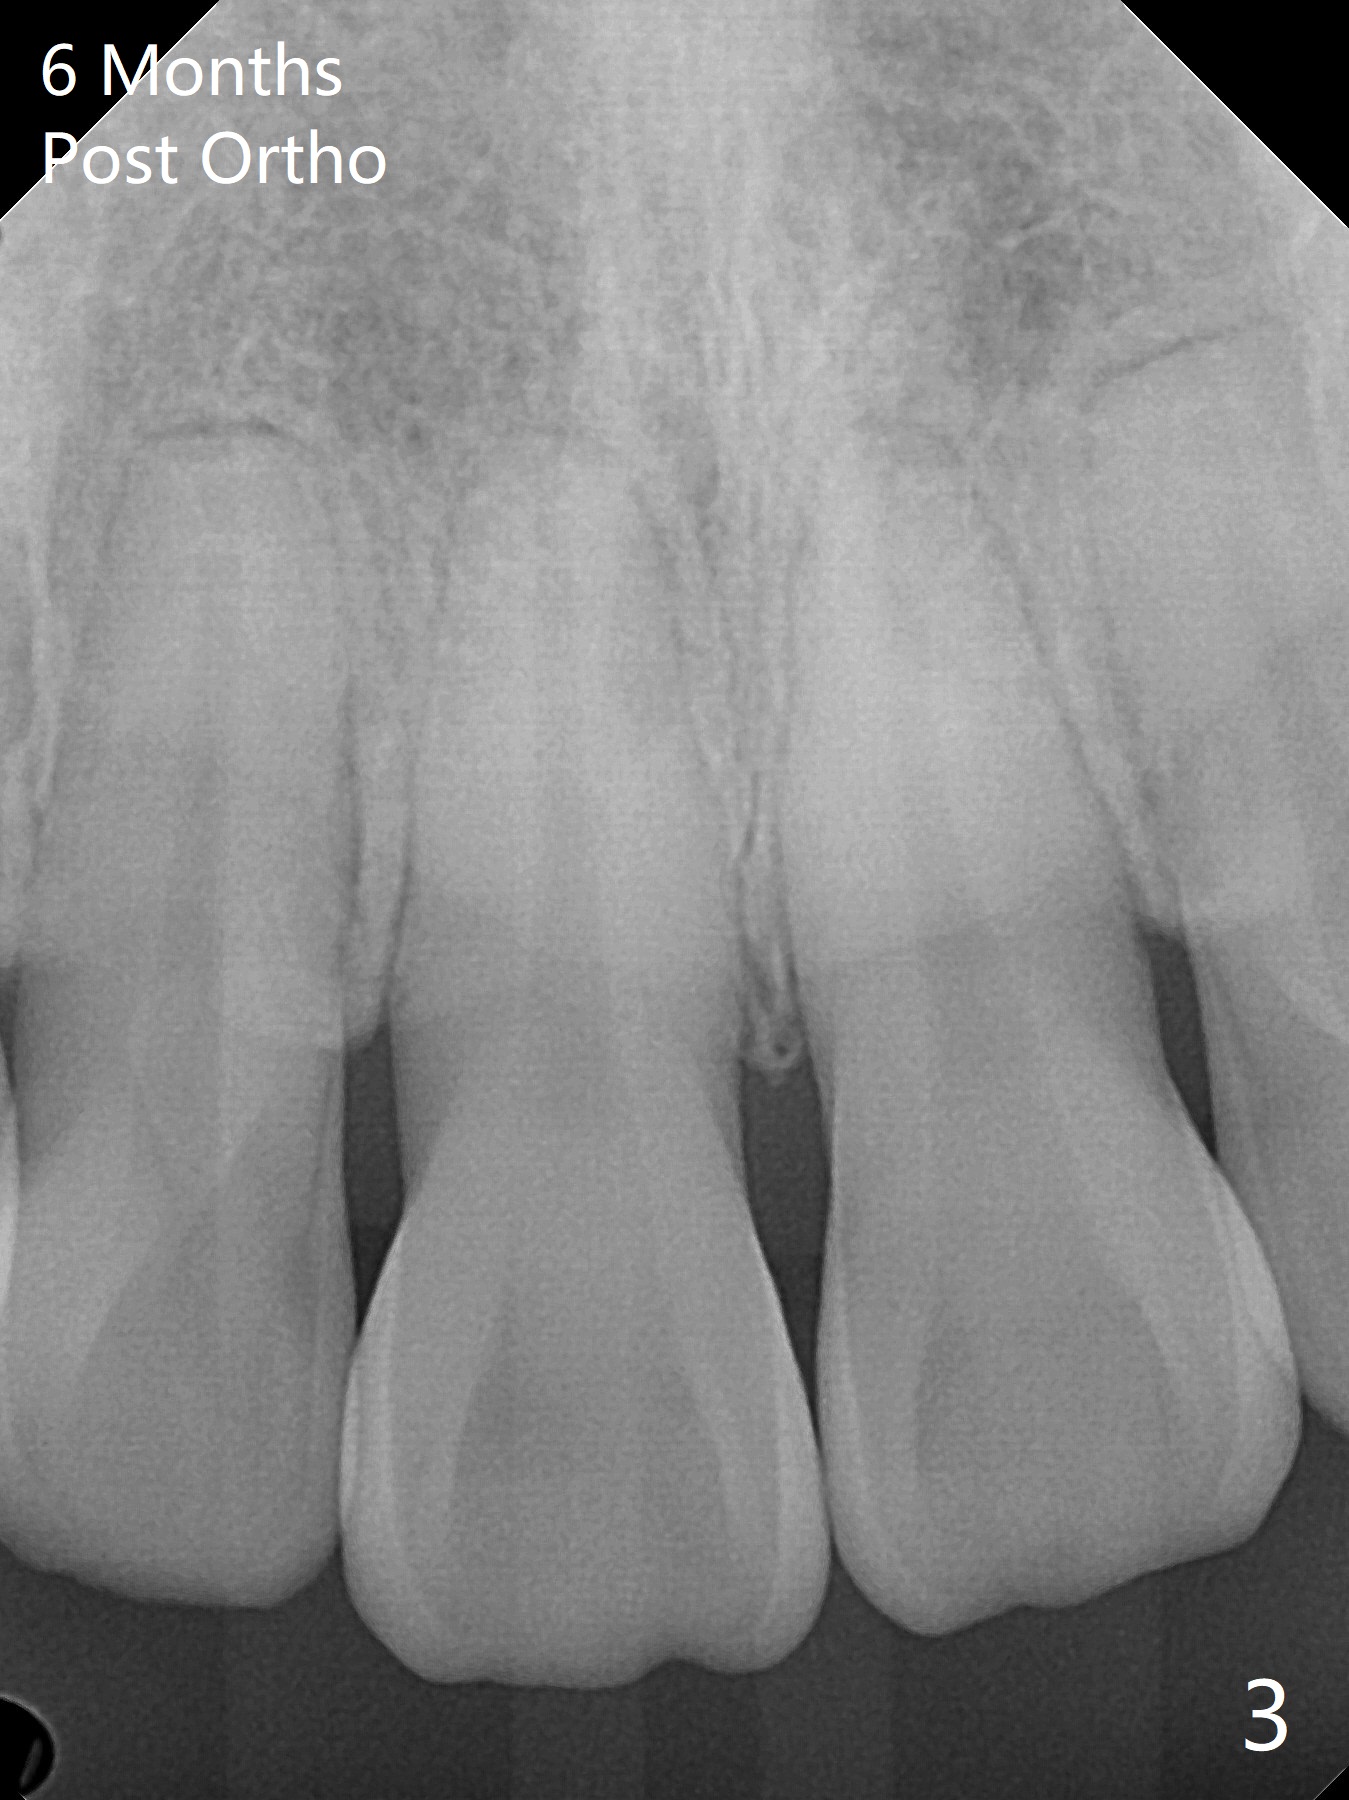

A 41-year-old woman with crowding (Fig.1) undergoes 2.5 year orthodontic treatment with extraction, leading to root resorption of the maxillary anterior teeth (Fig.2-4).